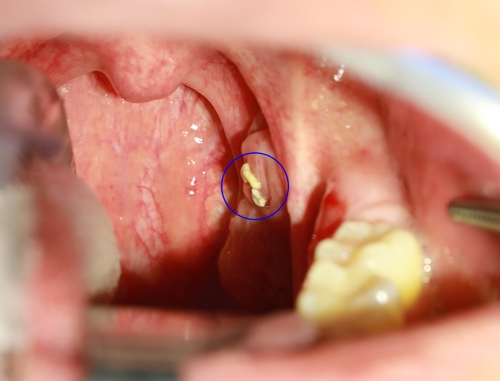

- 혀에 있는 설태를 작은 일회용 플라스틱 숟가락으로 긁어서 5초 후에 냄새를 맡아봅니다. 팁을 드리자면 배스킨라빈스에서 주는 분홍색 숟가락을 사용하면 좋습니다. 없다면 일회용 숟가락도 괜찮습니다.